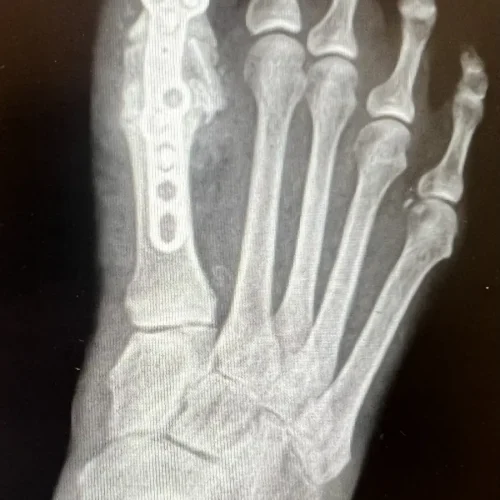

Surgical Intervention at Stepwell Institute is never a “one-size-fits-all” solution. We view surgery as a precise tool used to restore the natural biomechanics of the foot and ankle when non-invasive methods have reached their limit. Our philosophy centers on individualized surgical planning—using advanced imaging to map out the procedure before you ever enter the operating room. From correcting bunions and hammertoes to performing ligament repairs and fracture fixations, Dr. Yakov utilizes techniques designed to minimize trauma to the surrounding tissues, thereby reducing the risk of complications and ensuring a more stable, long-term result for our patients.

Stepwell Institute distinguishes itself by offering NJ patients access to the most advanced surgical modalities in modern podiatry. We specialize in Surgical Intervention, which utilize smaller incisions and specialized instruments to reduce post-operative pain and scarring. For more complex cases, we employ 3D-printed surgical guides and biological grafts to enhance the body’s natural healing ability. By choosing Stepwell Institute, you benefit from a specialized recovery plan where Dr. Yakov and our team prioritize early, safe mobilization. Our goal is to provide a definitive surgical solution that allows you to return to the active New Jersey lifestyle you love with confidence and strength. confidence and strength.

Our Case Study